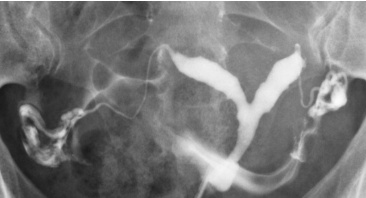

Um exame normal mostra uma cavidade uterina triangular com contornos lisos, tubas uterinas finas e sinuosas preenchendo-se progressivamente, e um espalhamento livre e bilateral do contraste na cavidade peritoneal.

HSG normal mostrando cavidade uterina, ambas as tubas preenchidas e espalhamento peritoneal livre (Cotte positivo bilateral).